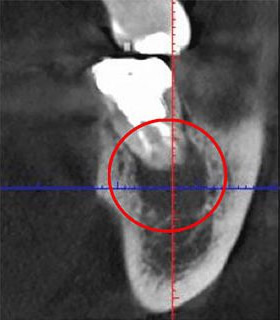

まず、実際に「根管」の画像をご覧ください。歯の内部にある黒い筋が根管で、その形状は非常に複雑です。特に狭い部分では直径が1mmにも満たないことがあります。

歯の内部にある根管は、肉眼では確認できません。その形状や状態を正確に知るためには、X線による検査が必要です。一般的な方法として知られているのが「レントゲン」ですが、当院では「CT」を使用しています。

レントゲンは2次元で撮影するのに対し、CTは口腔周囲を回転しながら撮影し、立体的かつ鮮明な画像を提供します。この特性により、患部の細部まで把握することができます。

以下の画像は同一の患部をCTとレントゲンで撮影したものです。

左側がCTで撮影した写真で、右側がレントゲンで撮影したものです。赤い丸で囲んだ部分には黒い影がありますが、これは炎症を示しています。しかし、右のレントゲン画像ではこの影が確認できません。

つまり、レントゲンのみの診断では、このような炎症を見逃してしまう可能性が高く、気づかない間に悪化し、最終的には抜歯に至るかもしれません。当院では、そのようなリスクを軽減するため、CTによる診断を徹底しています。